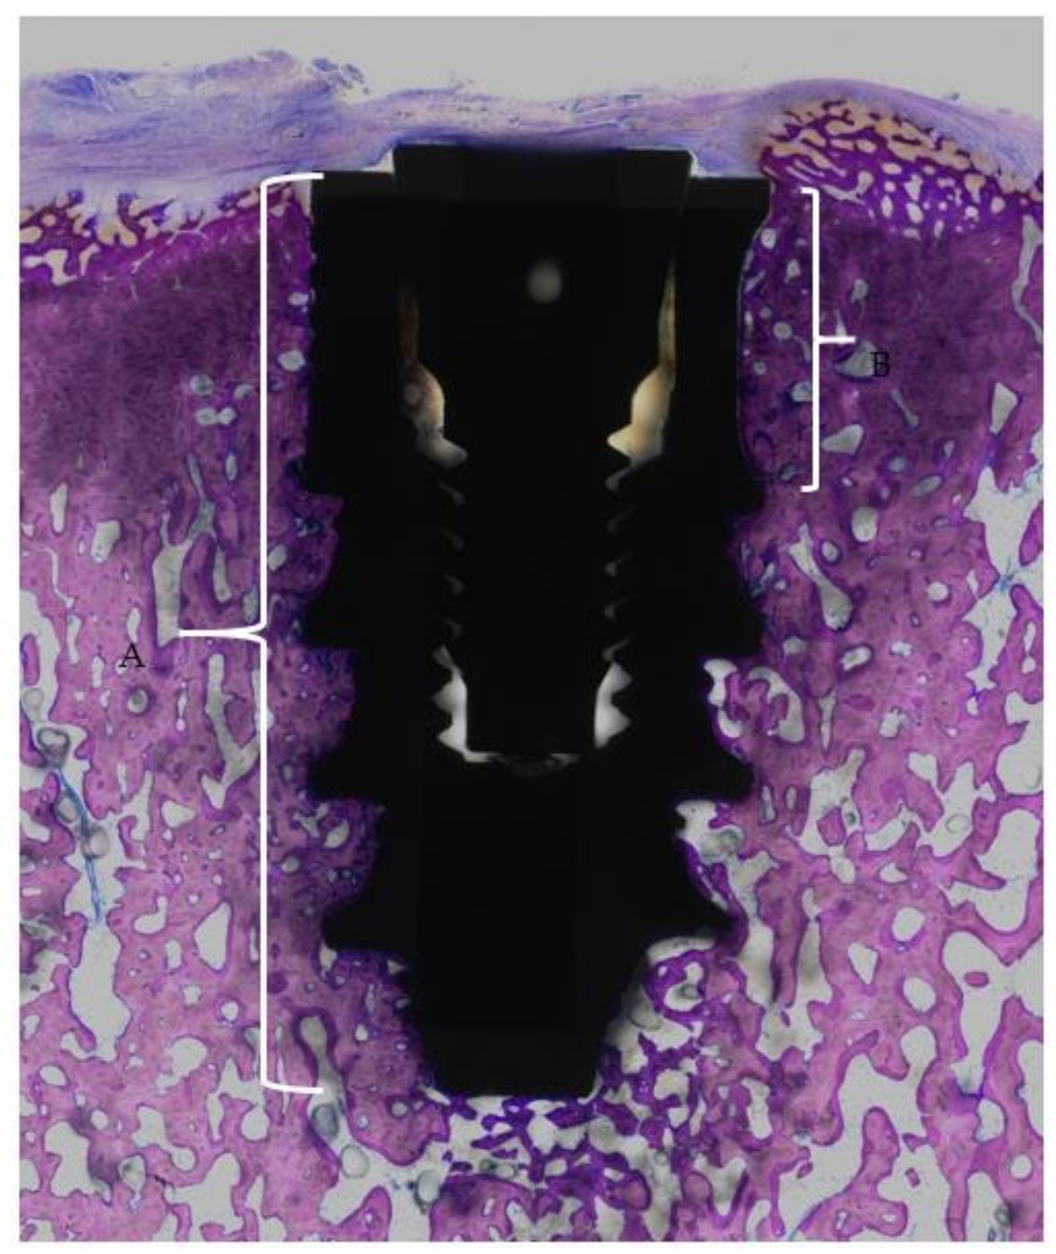

2.2. Histological Processing and Analysis

- The implant shoulder

- The apical end of the implant

- The coronal end of the flute

- The apical end of the flute